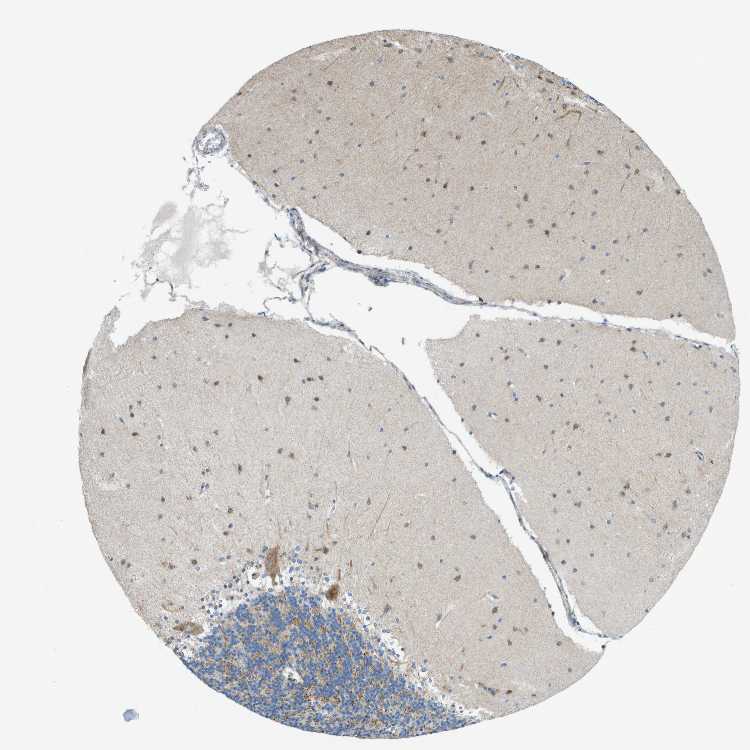

CEREBELLUM - Antibody stainingi

Antibody staining in the annotated cell types in the current human tissue is reported as not detected, low, medium, or high, based on conventional immunohistochemistry profiling in selected tissues. This score is based on the combination of the staining intensity and fraction of stained cells.

Each image is clickable and will lead to virtual microscopy that enables deeper exploration of all samples and also displays staining intensity scores, fraction scores and subcellular localization as well as patient and tissue information for each sample.

Antibody HPA015594

Purkinje cells Medium

Cells in granular layer Medium

Cells in molecular layer Medium